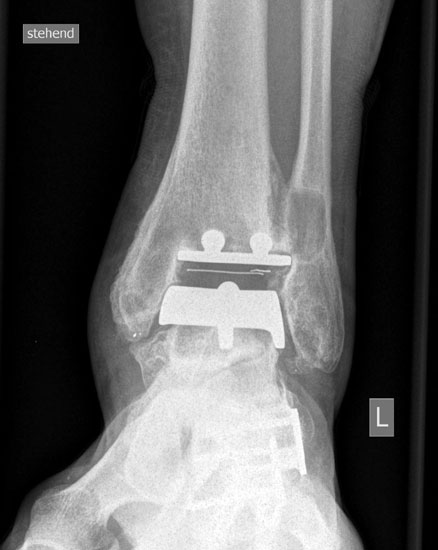

• Prothesenplanung anhand von Röntgenschablonen (Abb. 1 und 2).

• Röntgenkontrollen: 2 Tage postoperativ, 6 Wochen postoperativ; 3, 6, 12 Monate postoperativ, dann im Abstand von 12-18 Monaten.

Im Zeitraum zwischen 2006-2010 analysierten wir 118 SALTO-OSG-Prothesen bei 118 Patienten, 67 (56,8%) ohne zusätzliche Rückfußeingriffe, 51 (43,2%) mit zusätzlicher Rückfußkorrektur. Die Patienten wurden klinisch und radiologisch nachuntersucht. Das mittlere Follow up betrug 36 Monate.

Der AOFAS hindfoot score wies bei den Patienten ohne zusätzliche Rückfußkorrektur eine Steigerung von 40,8 Punkten präoperativ auf 86,2 Punkte postoperativ (2 Jahre postoperativ) auf. Bei den Patienten mit zusätzlicher Rückfußkorrektur wurde eine Steigerung von 39,0 auf 83,6 Punkte beobachtet.

Der Bewegungsumfang im OSG verbesserte sich bei den Patienten ohne zusätzlichen Korrektureingriff von präoperativ 25,4° auf 32,3° 24 Monate postoperativ (Dorsalextension von 2,9° auf 6,4°; Plantarflexion von 22,5° auf 25,7 °). Bei den Patienten mit vorbestehender Rückfußfehlstellung beobachteten wir nach Prothesenimplantation mit Rückfußkorrektur ebenfalls eine deutliche Steigerung des Bewegungsumfanges im OSG von präoperativ 22,2° auf 29,6° 24 Monate postoperativ (Dorsalextension von 0,9° auf 6,0°; Plantarflexion von 20,0° auf 23,6 °).